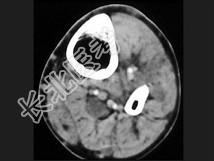

- 单项选择题男,35岁, 皮肤可见咖啡色素斑,关节疼痛, 结合图像,最可能的诊断是 ( )

A、骨肉瘤

B、骨转移瘤

C、神经纤维瘤

D、骨软骨瘤

E、纤维肉瘤